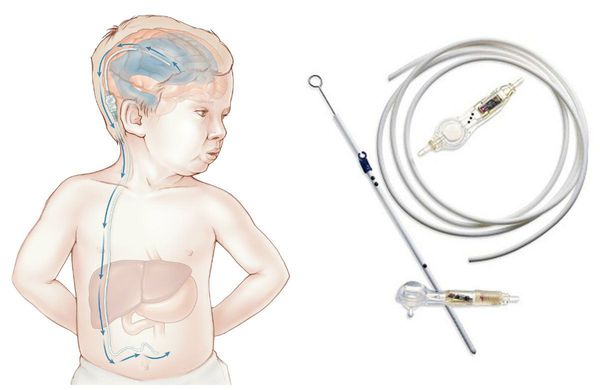

Вентрикуло-перитонеальный шунт: Показания и применение

Раздел: Фотоальбом решений